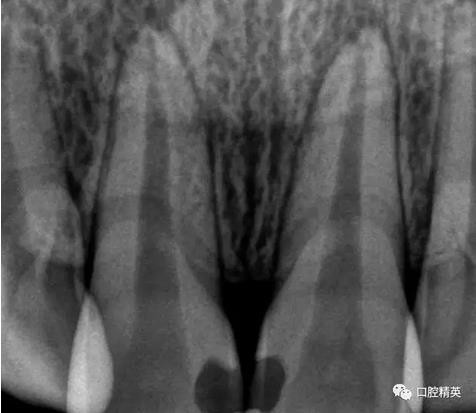

檢查:11,21近中鄰面可見樹脂類充填體,兩牙唇側(cè)根尖部有膿包狀突起,觸診疼痛,11,21無松動(dòng),叩診稍有不適,冷熱診檢查無反應(yīng),X-ray示11,21充填體底部近髓,根尖區(qū)無明顯異常影像。

術(shù)前檢查

齲洞低已近髓